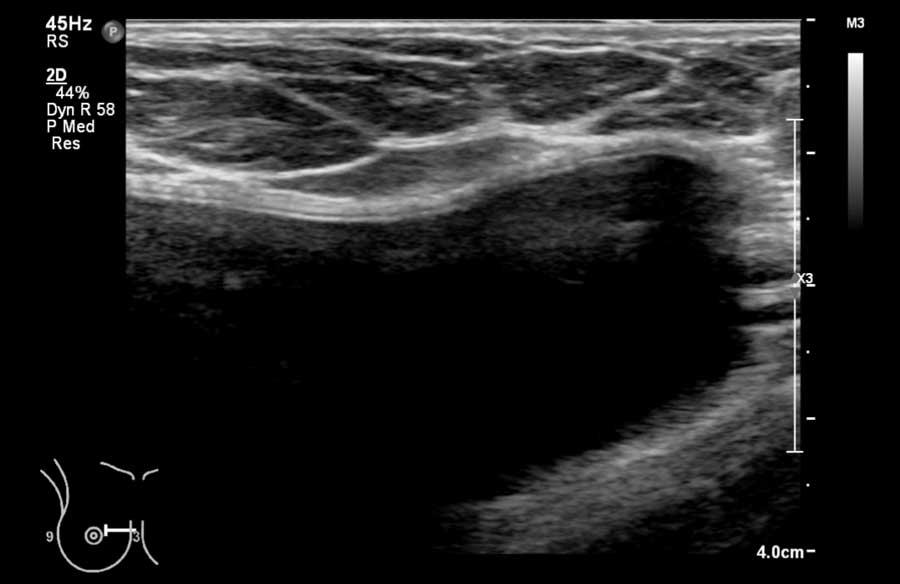

Đây là hình ảnh siêu âm bình thường của tuyến vú.

Lớp xám phía trên là da.

Tiếp theo là sự pha trộn giữa mô mỡ (tối hoặc giảm âm) và mô tuyến (xám sáng hoặc tăng âm).

Lớp có vân sọc phía sau mô vú là cơ ngực.

Phía sau hoặc sâu hơn so với xương sườn có một vùng đen hay bóng cản âm phía sau.

Phổi là lớp có thể quan sát sâu nhất.

Không khí trong phổi phản xạ hầu hết sóng âm, tạo ra một đường sáng hoặc tăng âm với bóng cản bẩn phía sau.